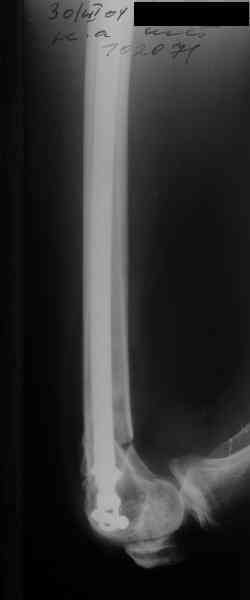

Re: Перелом диафиза и мыщелка бедра

Alexander Chelnokov 26 Октябрь 2006, 23:39

То есть оперировать уже можно. Какие планы обсуждаются на месте? Что именно вызывает разногласия? Что доступно в Ваших условиях?

Лучше бы уточнить характер повреждения наружного мыщелка бедра, есть ли его фронтальное раскалывание. Мы бы сделали репозицию мыщелка (если получится, то закрыто) с фиксацией спонгиозными винтами.

Не получится закрыто - наружный парапателлярный доступ, открытая репозиция, винты. И сделали бы закрытый интрамедуллярный остеосинтез бедра антгерадно. Если есть возможность, лучше использовать гвоздь, который позволит провести винты через мыщелок, т.е. очень близко к

дистальному концу.

Вполне возможен и ретроградный остеосинтез бедра, особенно если все-таки придется открывать сустав.